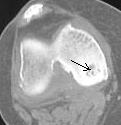

А вот примерно так выглядит это ложе на КТ, пока оно ещё не опустело (ложе в медиальном мыщелке помечено стрелками). Б-нь Кенига.

Конечно, Валентин Львович, я не обратил внимание на существование сайта, теперь добавлю туда несколько КТ-картинок.